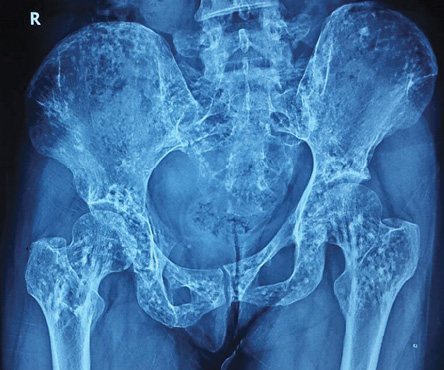

A 30-year-old woman presented with a three-year history of chronic low back pain without any other significant symptoms or history of any major illness. Family history was not significant for any major illness. Her systemic examination was unremarkable. X-ray of her pelvis showed multiple small round or oval sclerotic spots of 2–10 mm in size all over her skeleton [Figure 1]. Her blood investigations were within normal limits including her erythrocyte sedimentation rate and serum levels of alkaline phosphatase, calcium, and phosphorus. We performed an X-ray of both hands [Figure 2], which again showed multiple small round sclerotic spots. She was treated symptomatically for low back pain and is doing well.

Figure 1: X-ray of the pelvis showing multiple small round or oval sclerotic spots of 2–10 mm in size.

Routine blood examination including serum calcium, phosphorus, and alkaline phosphatase will be normal. X-ray shows multiple small, well-defined, widely symmetrically distributed round or oval sclerotic spots of 2–10 mm in size all over the skeleton, with a propensity for epiphyseal and metaphyseal involvement.1,3 The preferred sites of radiological involvement include: the phalanges (100%), carpal bones (97.4%), metacarpals (92.5%), feet phalanges (87.2%), metatarsals (84.4%), tarsal bones (84.6%), pelvis (74.4%), femur (74.4%), radius (66.7%), ulna (66.7%), sacrum (58.9%), humerus (28.2%), tibia (20.5%), and fibula (2.8%).5 It has to be differentiated from osteoblastic metastasis, tuberous sclerosis, mastocytosis, melorheostosis, osteopathiastriata, and synovial chondromatosis. Uniform size, symmetrical periarticular distribution with a normal bone scan or slightly increased activity, normal alkaline and acid phosphatase help to differentiate osteopoikilosis from osteoblastic metastasis where there is asymmetry, axial skeleton involvement, bony destruction, and positive bone scan. The bony lesions in tuberous sclerosis and mastocytosis are asymmetric, less well defined, and show lesser periarticular preference compared to osteopoikilosis, helping to differentiate these. Osteopoikilosis usually requires symptomatic treatment only.